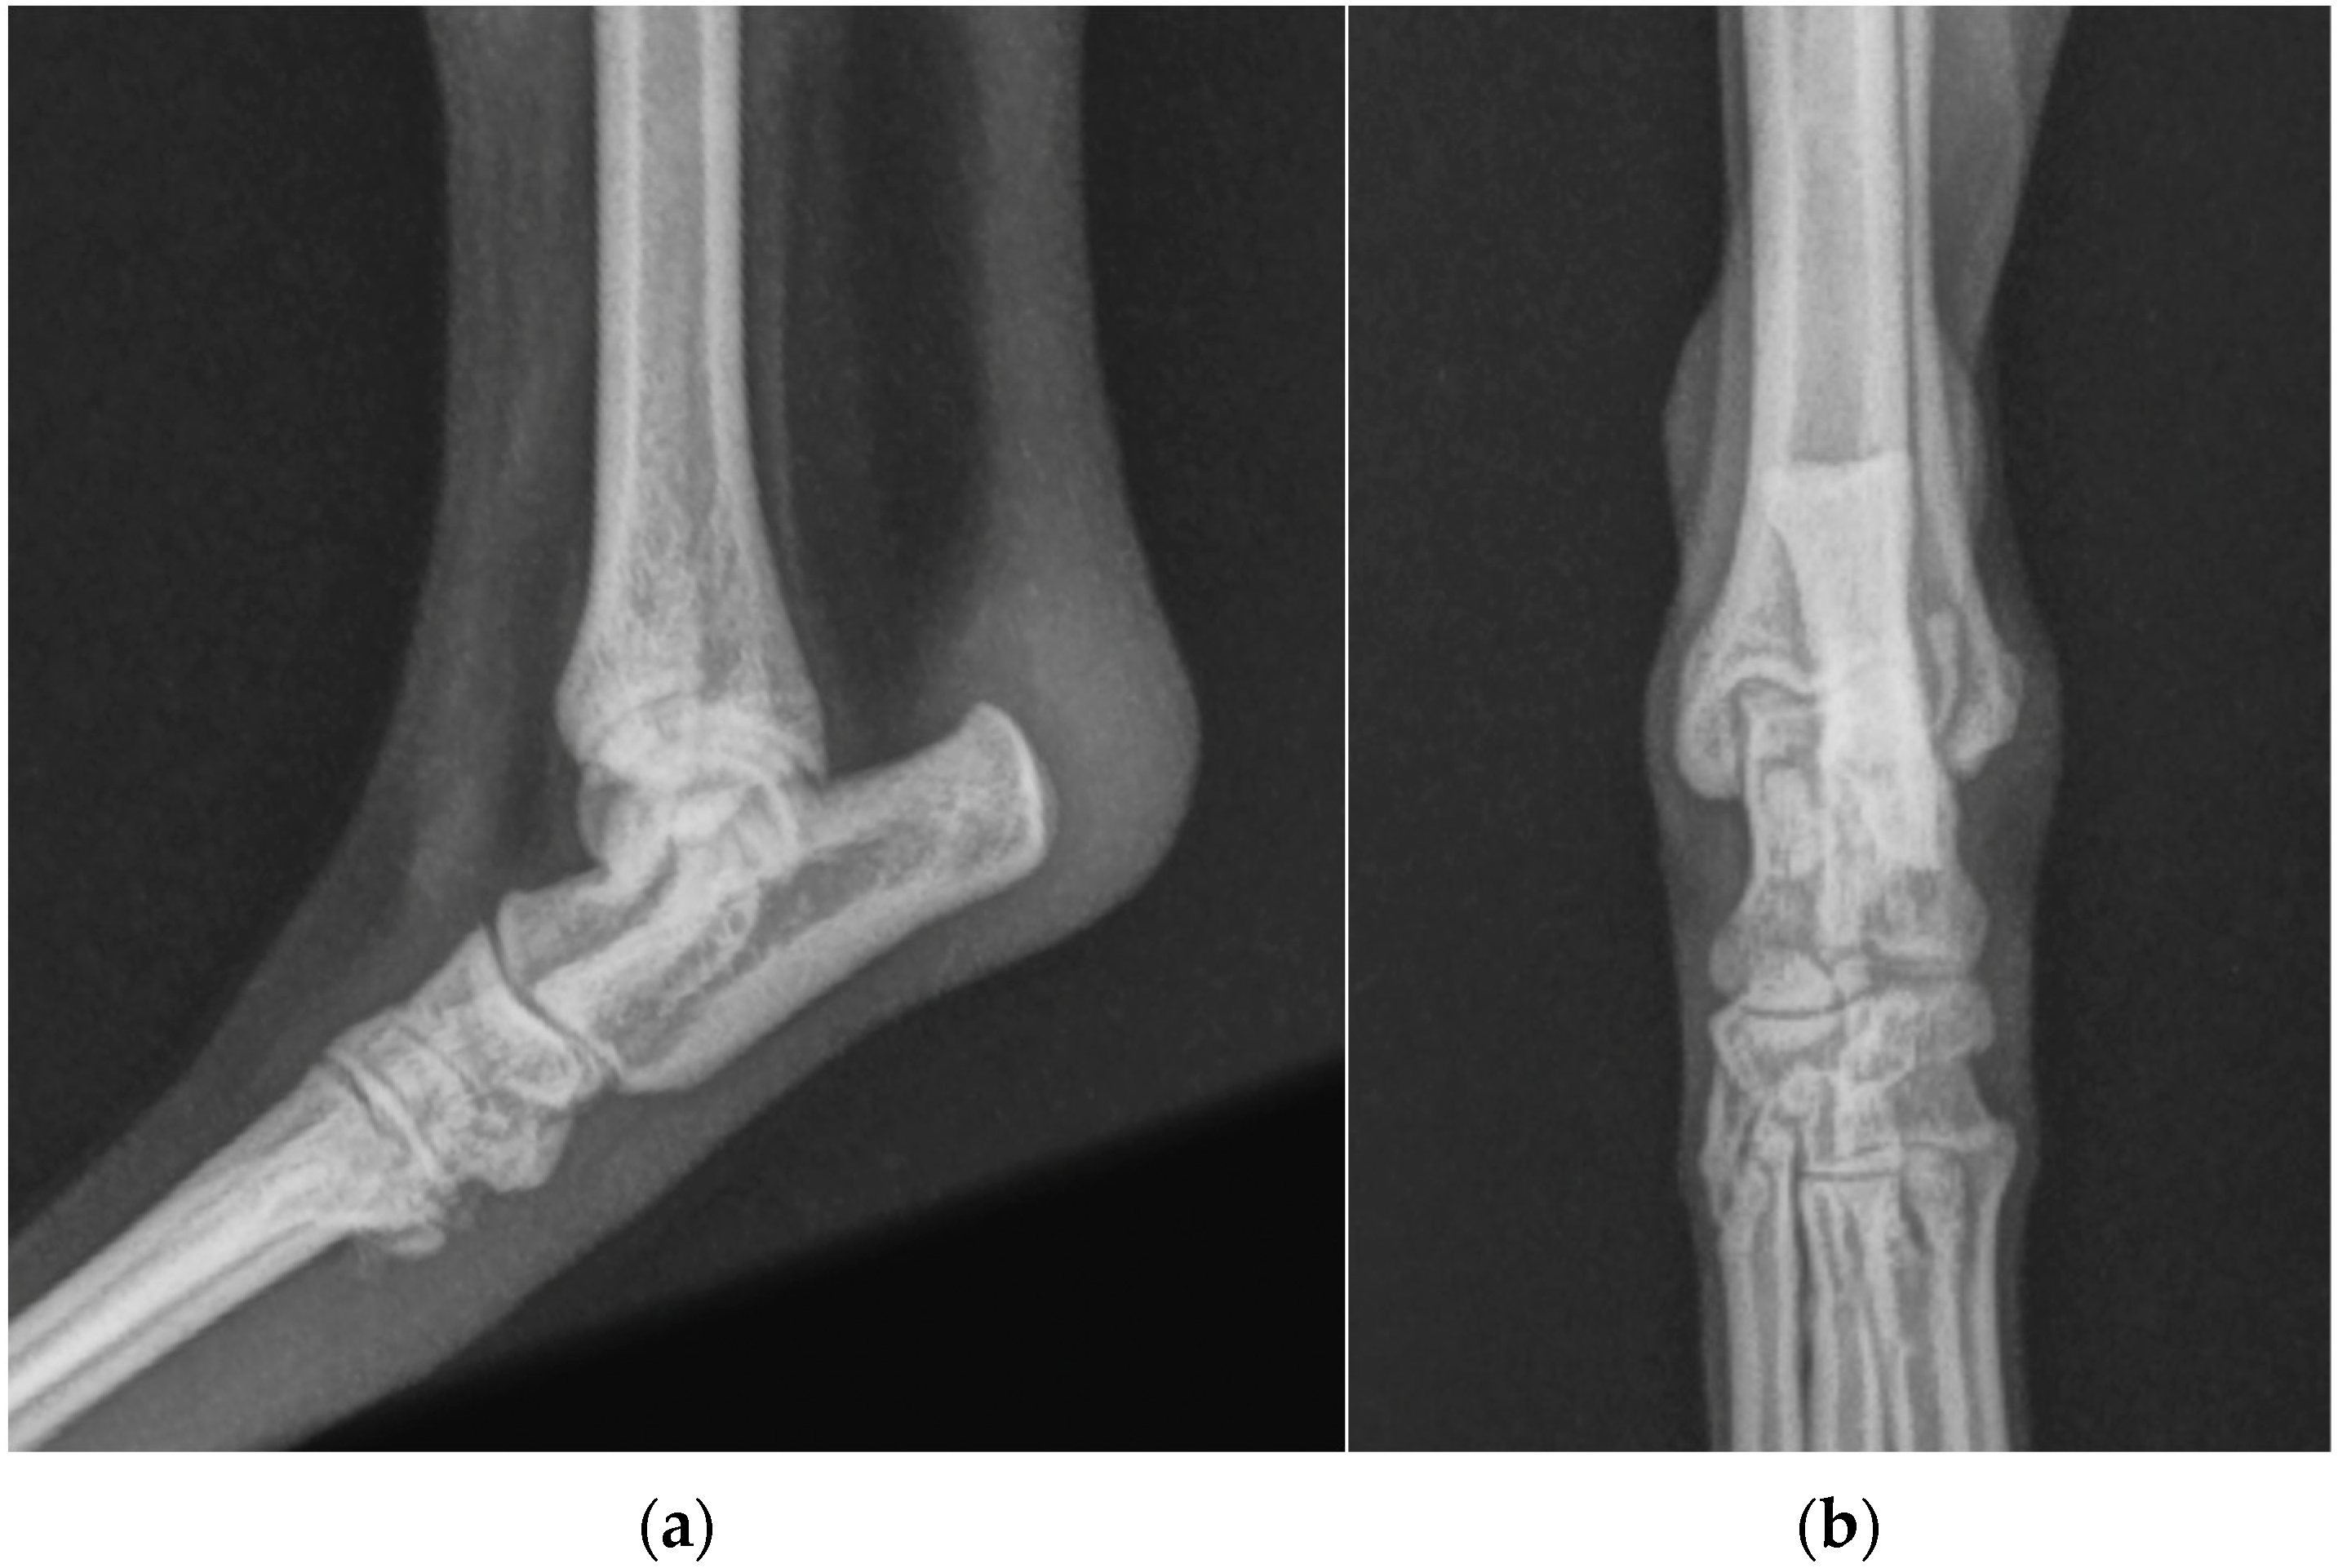

One years after surgery, the patient was presented with the same clinical evidence in the right hind limb (grade II) [19]. SDF tendon lateral luxation of the right hind limb was diagnosed following a clinical and radiographic examination similar to the previous one (Figure 2). The SDF tendon of the left hind limb was perfectly in place, and dorsoplantar and mediolateral radiographic images of the tibial-tarsal joint did not detect mild radiopacity of pericalcaneal soft tissue and rearrangement of bone tissue at the tip of the calcaneal tuberosity without secondary osteoarthrosis. The dog underwent surgery and postoperative treatment as described previously. At the follow-up clinic and radiographic examination, 4 and 8 weeks and 12 months after the intervention, no complications were reported (Figure 3).

Figure 2. (a) Mediolateral and (b) dorsoplantar radiographic projections of the right tibial-tarsal joint’s highlighted radiopacity of pericalcaneal soft tissue without osteoarticular changes.